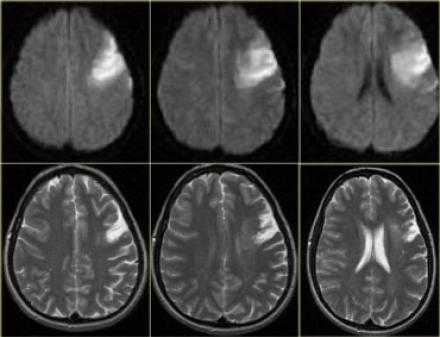

Диффузно-взвешенное изображение.

DWI наиболее чувствительна к инсульту. В результате цитотоксического отека возникает дисбаланс внеклеточной воды к Броуновскому движению, поэтому данные изменения выявляются отлично на DWI. В норме протоны воды диффундируют внеклеточно, поэтому теряется сигнал. Высокая интенсивность сигнала на DWI указывает на ограничение протонов воды диффундировать внеклеточно.

Представлены ДВИ инфаркт передней, задней, средней мозговой артерии.

Есть некоторая гиподенсность и отек в левой лобной доли со старостью борозд в сравнении с контр-латеральной стороной. Далее DWI снимки того же пациента. После просмотра DWI нет сомнения, что это инфаркт. Именно поэтому DWI называют инсульт последовательностью.

Когда мы сравниваем результаты на T2WI и DWI во времени, мы заметим следующее: В острой фазе T2WI норма, но со временем зона инфаркта станет гиперинтенсивной. Гиперинтенсивность на T2WI достигает своего максимума между 7 и 30 дней. После этого сигнал начинает угасать. На DWI гиперинтенсивная область в острой фазе, а затем становится более интенсивной с максимумом на 7 дней. На DWI у пациента с инфарктом головного мозга визуализируется гиперинтенсивная область примерно на 3 недели после начала заболевания (при инфаркте спинного мозга на DWI визуализируется гиперинтенсивная область на одну неделю!). На ADC будет сигнал низкой интенсивности с минимальной интенсивностью в первые 24 часа, после сигнал будет увеличиваться в интенсивности и, наконец, становится максимально интенсивным в хроническую стадию.